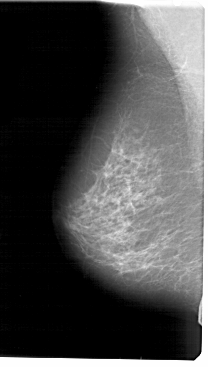

A_1458_1.RIGHT_MLO

RIGHT_MLO LINES 5491 PIXELS_PER_LINE 2926 BITS_PER_PIXEL 12 RESOLUTION 43.5 OVERLAY